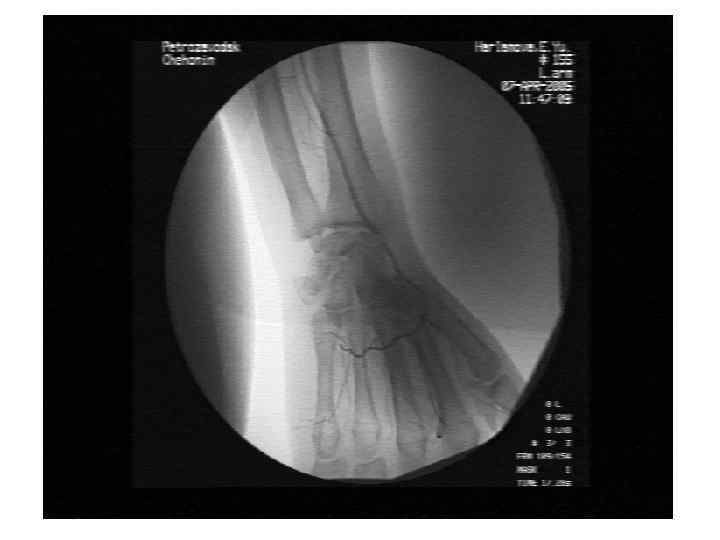

Эссенциальная криоглобулинемия